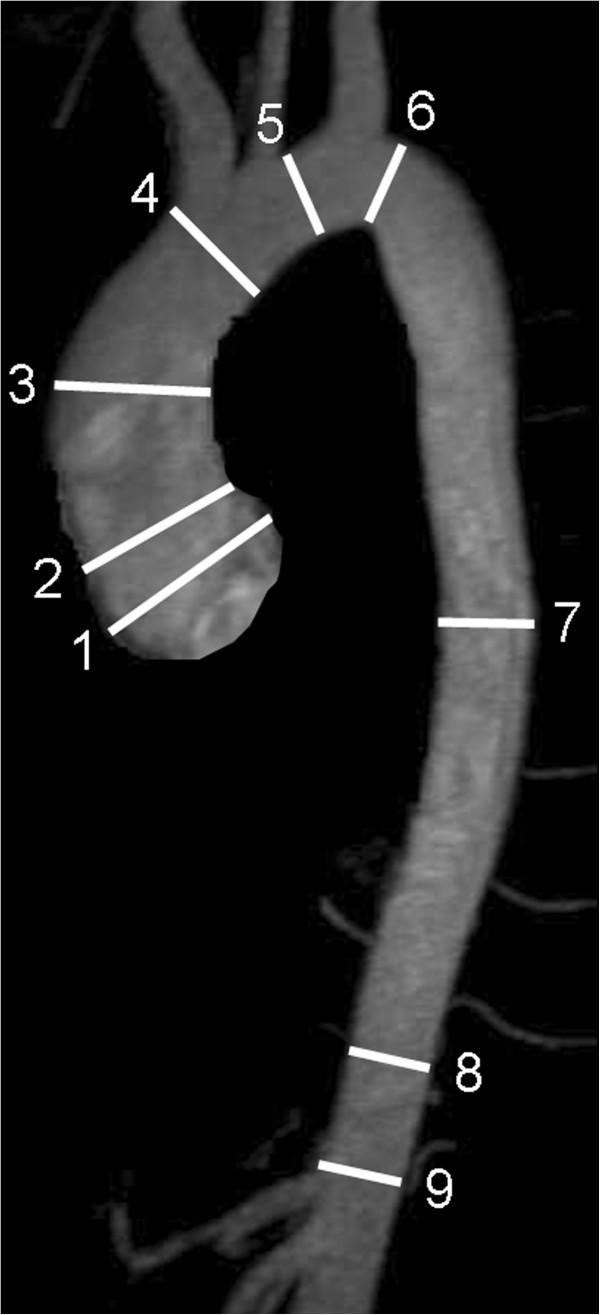

Standardized image interpretation and post processing in cardiovascular magnetic resonance: Society for Cardiovascular Magnetic Resonance (SCMR) board of trustees task force on standardized post processing.

With mounting data on its accuracy and prognostic value, cardiovascular magnetic resonance (CMR) is becoming an increasingly important diagnostic tool with growing utility in clinical routine. Given its versatility and wide range of quantitative parameters, however, agreement on specific standards for the interpretation and post-processing of CMR studies is required to ensure consistent quality and reproducibility of CMR reports. This document addresses this need by providing consensus recommendations developed by the Task Force for Post Processing of the Society for Cardiovascular MR (SCMR). The aim of the task force is to recommend requirements and standards for image interpretation and post processing enabling qualitative and quantitative evaluation of CMR images. Furthermore, pitfalls of CMR image analysis are discussed where appropriate.